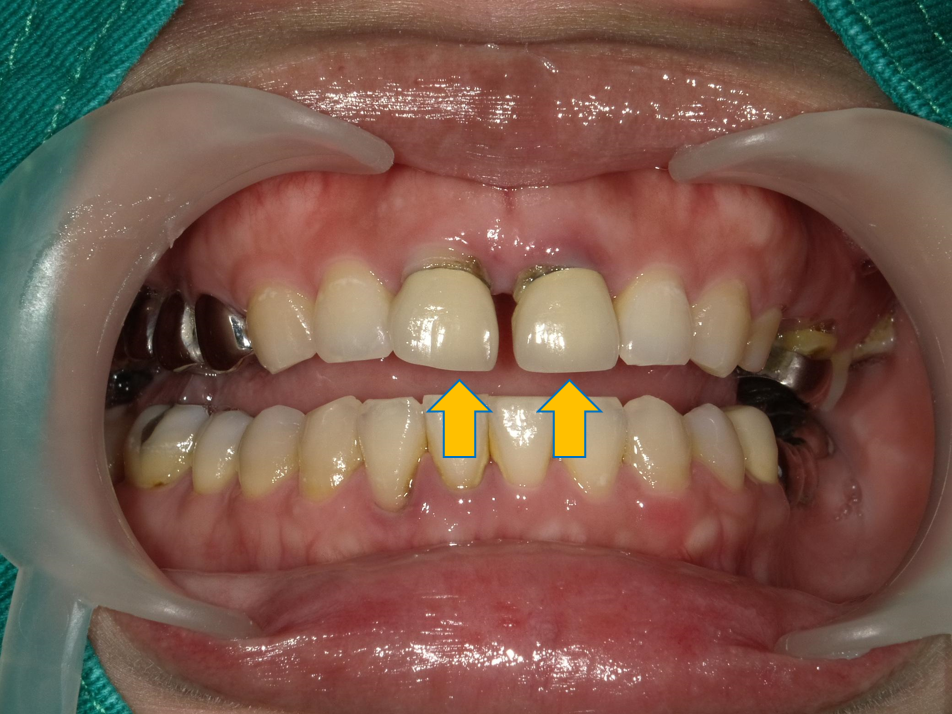

案例 2 術前(Before)

牙縫過大,舊有假牙不密合